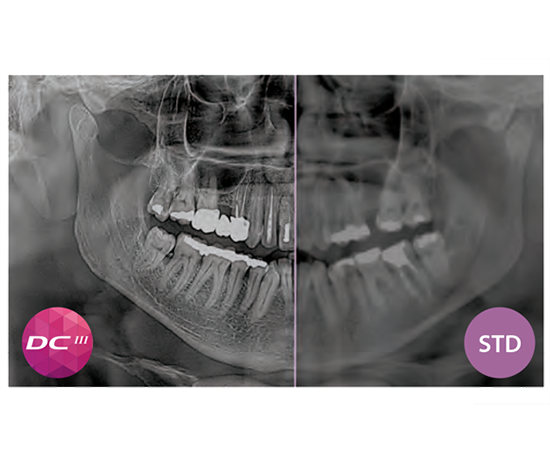

Il est possible de remplacer le capteur 2D standard par le capteur DCIII à conversion directe innovant pour des images super HD à faible dose.

La technologie DCIII applique le capteur à conversion directe innovant qui a révolutionné l’imagerie 2D aux filtres PiE (Powerful image Enhancer). Les systèmes standards prévoient une conversion des rayons X en lumière visible, qui est traduite à son tour en signaux électriques pour donner naissance à l’image numérique. À l’inverse, avec la technologie DCIII, le capteur reçoit et génère directement les rayons X, ce qui augmente la sensibilité et l’efficacité sans perte de détails. Cela permet d’obtenir des images haute résolution avec un niveau de contraste supérieur et à faible dose, mais également extrêmement détaillées, y compris des protocoles de balayage rapide à très faible dose tels que QuickCEPH ou QuickPAN.

Le capteur 2D est facile à déplacer et interchangeable. Vous pouvez choisir tout de suite, ou dans un deuxième temps entre le capteur STANDARD CMOS (Csl) - qui génère des images nettes, uniformes et en très haute définition tout en maintenant une faible dose d’irradiation - et le capteur révolutionnaire et encore plus performant CMOS (Cd-Te) à conversion directe (DCIII) qui permet non seulement d’obtenir des images d’excellente résolution et à très faible dose mais optimise également au maximum les performances de Hyperion X9 pro.

La technologie DCIII innovante - qui optimise la profondeur de foyer et augmente le niveau de contraste et, en conséquence, le pouvoir de résolution réel - permet d’obtenir un panoramique SuperHD à partir d’un ensemble de données extrêmement vaste, pour obtenir un MultiPAN à 11 couches. Particulièrement utile en cas de morphologies complexes.